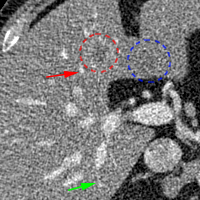

To show the denoising effect of the selected networks, we took two representative slices as shown in Figs. 5 and 7. And Figs. 6 and 8 are the zoomed regions-of-interest (ROIs) marked by the red rectangles in Figs. 5 and 7. All the networks demonstrated certain denoising capabilities. However, CNN-MSE blurred the images and introduced waxy artifacts as expected, which are easily observed in the zoomed ROIs in Figs. 6e and 8e. WGAN-MSE was able to improve the result of CNN-MSE by avoiding over-smooth but minor streak artifacts can still be observed especially compared to CNN-VGG and WGAN-VGG. Meanwhile, using WGAN or GAN alone generated stronger noise (Figs. 6g and 8g) than the other networks enhanced a few white structures in the WGAN/GAN generated images, which are originated from the low dose streak artifact in LDCT images, while on the contrary the CNN-VGG and WGAN-VGG images are visually more similar to the NDCT images. This is because the VGG loss used in CNN-VGG and WGAN-VGG is computed in a feature space that is trained previously on a very large natural image dataset [48]. By using VGG loss, we transferred the knowledge of human perception that is embedded in VGG network to CT image quality evaluation. The performance of using WGAN or GAN alone is not acceptable because it only maps the data distribution from LDCT to NDCT but does not guarantee the image content correspondence. As for the lesion detection in these two slices, all the networks enhance the lesion visibility compared to the original noisy low dose FBP images as noise is reduced by the different approaches.

As for iterative reconstruction technique, the reconstruction results depend greatly on the choices of the regularization parameters. The implemented dictionary learning reconstruction (DictRecon) result gave the most aggressive noise reduction effect compared to the network outputs as a result of strong regularization. However, it over-smoothed some fine structures. For example, in Fig. 8, the vessel pointed by the green arrow was smeared out while it is easily identifiable in NDCT as well as WGAN-VGG images. Yet, as an iterative reconstruction method, DictRecon has its advantage over post-processing method. As pointed by the red arrow in Fig 8, there is a bright spot which can be seen in DictRecon and NDCT images, but is not observable in LDCT and network processed images. Since the WGAN-VGG image is generated from LDCT image, in which this bright spot is not easily observed, it is reasonable that we do not see the bright spot in the images processed by neural networks. In other words, we do not want the network to generate structure that does not exist in the original images. In short, the proposed WGAN-VGG network is a post-processing method and information that is lost during the FBP reconstruction cannot easily be recovered, which is one limitation for all the post-processing methods. On the other hand, as an iterative reconstruction method, DictRecon algorithm generates images from raw data, which has more information than the post-processing methods.